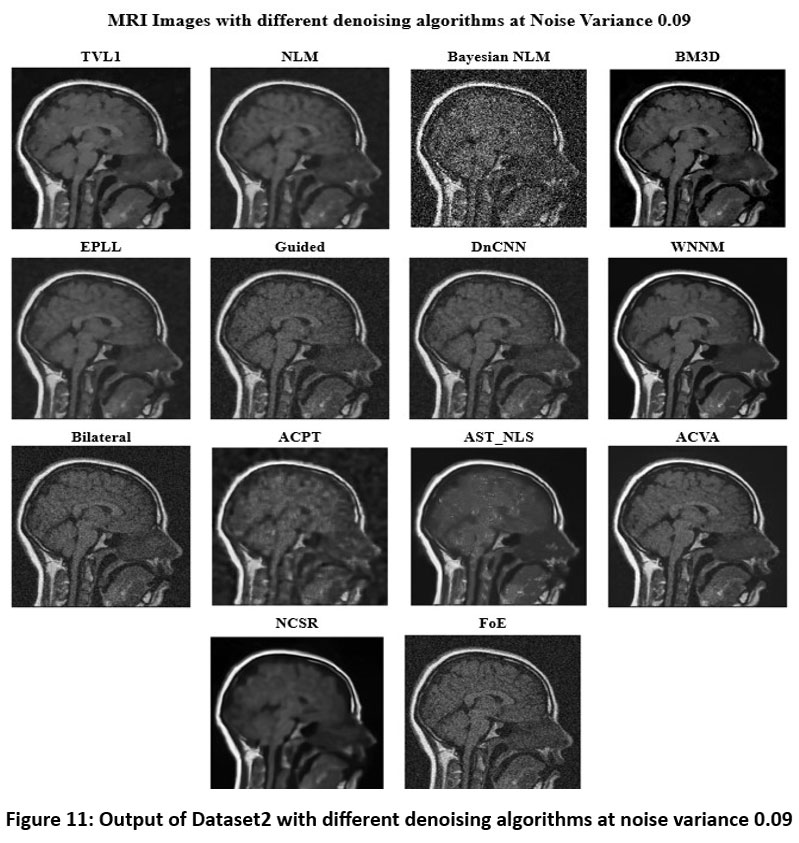

![]() |

Figure 11: Output of Dataset2 with different denoising algorithms at noise variance 0.09 |

Figure 11 depicts several denoising algorithms at a high noise variance of 0.09. BM3D is one of the most successful algorithms among them because it saves many anatomical features in the image with accuracy as well as retains high picture clarity. Other such effective models include DnCNN and WNNM, both of which return very sharp pictures with almost zero blur and intense contrast preservation. Bayesian NLM performs miserably and results in a highly noised image with significant graininess. Though NLM produces a good decrease in noise at this noise variance, the residue graininess would make it less suitable for application in clinics at this variance. Guided filtering, EPLL, and bilateral filtering over smoothed the image and, hide the small features. While ACPT produces a blurred output, which reduces the interpretability of pictures, ACVA and AST_NLS find a reasonable balance between denoising and structure preservation. TVL1 suppresses noise well but is over-smoothed, losing important medical information. In this high-noise environment, NCSR and FoE perform worse. While FoE fails to effectively reduce noise, leading to a grainy and less useful output.